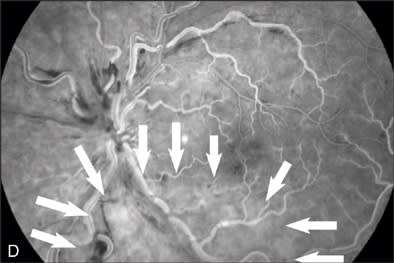

At the 5-month follow-up visit in February 2009, corrected visual acuity remained 20/20 in the left eye, with normal ocular pressure in both eyes. There were no rubeosis irides in either eye. Fundus examination appeared normal in the right eye with improvement in the appearance of the retinal vasculature in the left (Figure 2A). Fluorescein angiography of the left eye (Figure 2B to 2E) showed resolution of the CRVO characteristics (dilated, tortuous retinal veins, intraretinal hemorrhages, peripheral retinal non-perfusion areas) with no microvascular leakage at the macula. Spectral OCT confirmed no cystoid macular edema (Figure 2E).

Figure 2 A–G |

Figure 1F demonstrates the changes of oximetry between the 2 visits. The arterial oximetry changed from blue to red (red arrow), the venous oximetry changed from green to blue (yellow arrow). The non-perfusion area in the Figure 1F (appeared in blue) disappeared as shown in the follow-up visit report (Figure 2F), this was well correlated with the changes in the FA images in Figures 1D and 2D. The change to the nerve fiber layer infarction area was also observed on the oximetry, where it primarily appeared in white (Figure 1F, black arrow) then it disappeared in the follow-up visit report (Figure 2F), this change was also well correlated with the change between the red-free images (Figure 1B, arrow outlined, and Figure 2B).

The segmental blood-flow reports (Figures 1G and 2G) were also compared and described in the details of changes. In the area in the Figure 1G (white arrow outlined) that appeared to be poorly perfused, blood-flow velocities were depressed compared to results of the same area in the follow-up visit report (Figure 2G). The segmental blood-flow value under the nerve fiber layer infarction area (Figure 1G, black arrow) had no significant change between the 2 visits. The average blood-flow values of the entire retina at the follow-up visit were 3.03 and 2.08 mm/sec for artery and vein respectively, compared with the values at the first visit of 1.11 and 1.00 mm/sec for arteries and veins respectively.